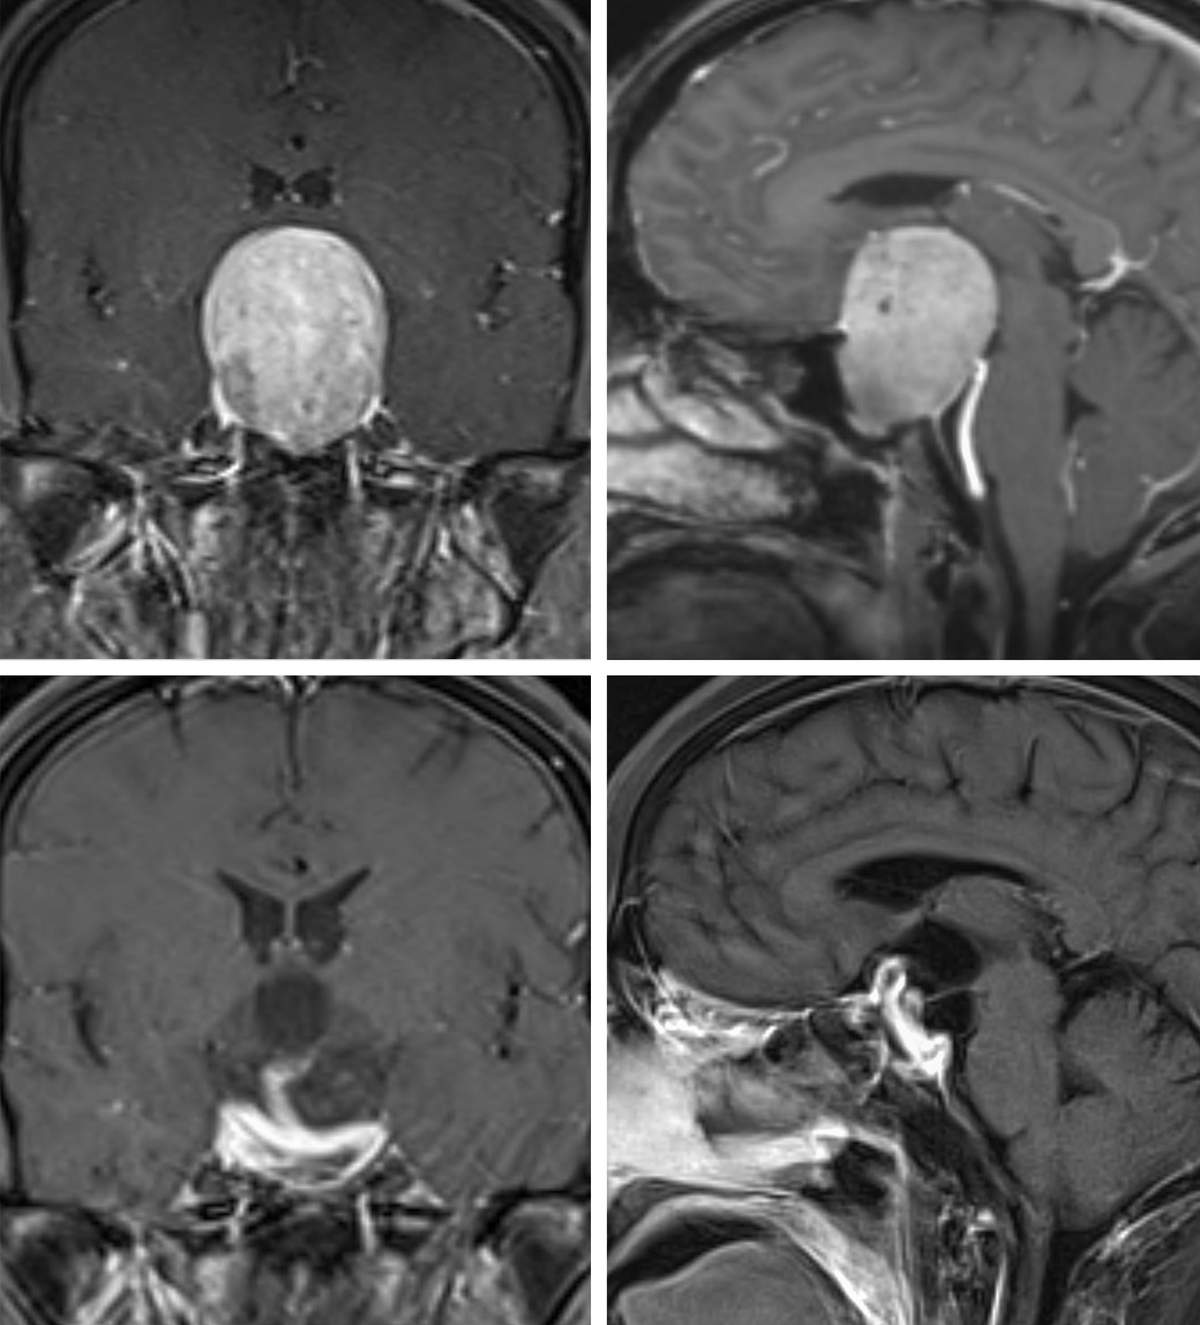

MRI with contrast would diagnose correctly the size and extension of Pituitary Brain Tumors and the extent of upwards visual nerve compression and sidewards cavernous sinus invasion by the tumor.

Some pituitary brain tumors at presentation are giant and cannot be taken out through the nose and require brain surgery. They may be difficult to remove completely and their prognosis is not as good as most of the Pituitary Tumors.